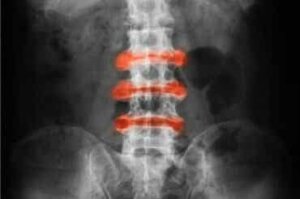

Selkärankareuma (ankyloiva spondyliitti) on niveltulehdus, jota esiintyy pääasiassa selän ja lantion nivelissä. Akuutit vaivat ja jäykkyys paranevat yleensä liikkeen myötä, ja paikalleen jääminen voi pahentaa sitä.